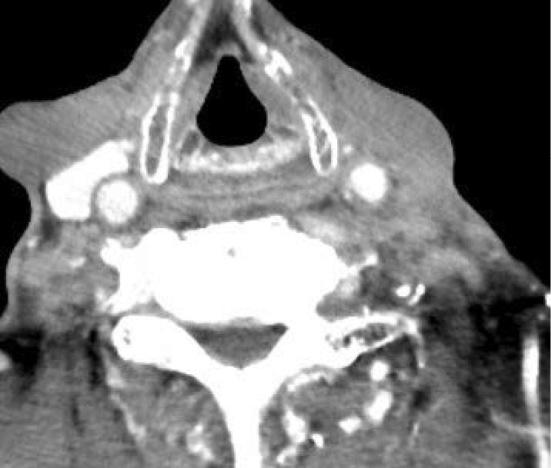

We herein report a case of glossopharyngeal neuralgia with repeated syncope caused by the recurrence of esophageal carcinoma. The typical symptoms of glossopharyngeal neuralgia are paroxysmal, stabbing, electric shock-like pain in the pharynx and/or base of the tongue on swallowing and talking. In addition, syncope can also be caused by glossopharyngeal neuralgia. The diagnosis of glossopharyngeal neuralgia is not always easy because of its rarity. In the present case, we suspected that repeated syncope was caused by glossopharyngeal neuralgia due to the recurrence of esophageal carcinoma. Concurrent chemoradiation therapy was effective in reducing the tumor size, which resulted in the complete resolution of the symptoms.

我们在此报告一例因食管癌复发导致反复晕厥的舌咽神经痛病例。舌咽神经痛的典型症状是吞咽和说话时咽部和/或舌根处阵发性、刺痛、电击样疼痛。此外,舌咽神经痛也可导致晕厥。由于其罕见性,舌咽神经痛的诊断并不总是容易的。在本病例中,我们怀疑反复晕厥是由食管癌复发引起的舌咽神经痛所致。同步放化疗有效缩小了肿瘤大小,症状得以完全缓解。